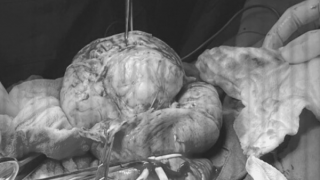

BS Nguyễn Văn Tiến cho hay, đây là một khối u có trọng lượng nặng gần 15kg được bóc tách thành công khỏi cơ thể người bệnh. Ca mổ khối u quá khủng đã làm kinh ngạc cả kíp mổ và những người xem.